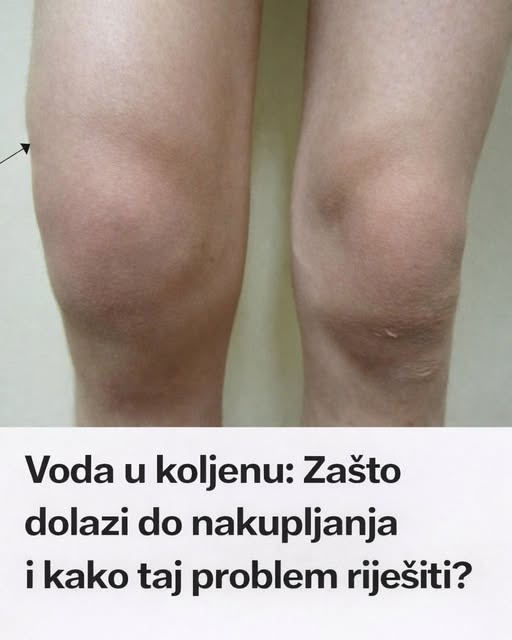

U današnjem članku vam pišemo o čestom zdravstvenom problemu koji se može pojaviti u bilo kojem uzrastu – nakupljanju vode u koljenu. Saznajte…

Mnogi nisu ni svjesni što se zapravo događa kada im koljeno počne oticati i postane bolno.

Pojava tekućine u zglobu koljena nije samo estetski problem, već signalizira da se u tijelu nešto događa. Osim što je neugodno, može značajno ometati svakodnevne aktivnosti.

Koljeno je jedan od najvećih i najopterećenijih zglobova u ljudskom tijelu, svakodnevno sudjelujući u pokretima poput hodanja, trčanja i penjanja uz stepenice. Kada dođe do nakupljanja tekućine, to često znači da se zglob reagira na neku vrstu iritacije, upale ili oštećenja. Zbog toga, voda u koljenu nije bolest sama po sebi, već simptom koji ukazuje na dublji problem, bilo da je riječ o povredi, prekomjernom opterećenju ili nekom zdravstevnom poremećaju. Uz to, često se javljaju bolovi, osjećaj pritiska i smanjena pokretljivost, što može dodatno otežati obavljanje svakodnevnih aktivnosti.